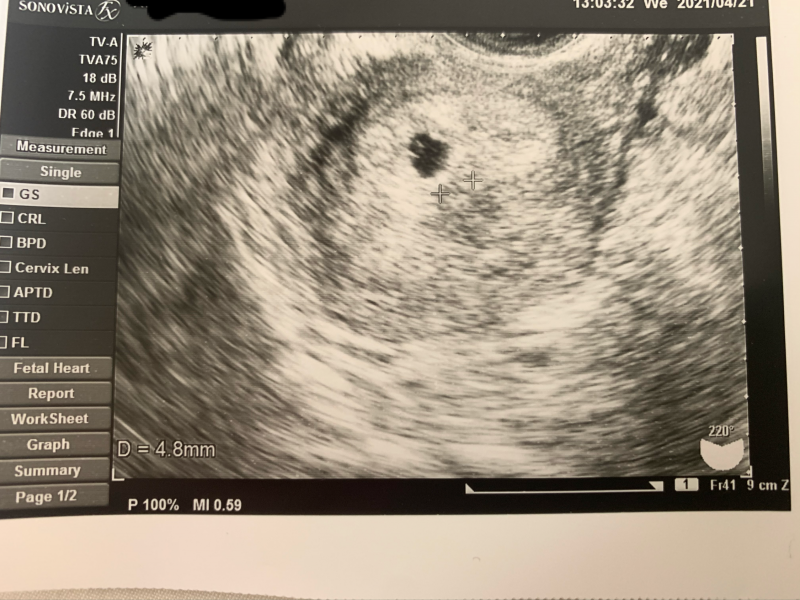

Web本日病院受診をし、胎嚢確認はできましたが小さいと言われました。 推定5週4日で69mmでした。 小さいから流産の可能性もある、 このまま成長してくれれば心配はなくなる また2週間後に来てくださいとのことでした。 今日妊娠発覚後初めての診察でした。 最終月経日から数えると5週3日目です。 胎嚢確認はできたのですが、47mmでした。 先生には「小さいね~」とWeb 「胎嚢サイズ小さい? 大丈夫? 」ってこと。 ネットで検索してみると、 妊娠5週の胎嚢の平均サイズは、10mm~25mm程度と書いてある。 三重大学医学部の資料による

Web 6週の胎嚢の大きさは約2cm 胎嚢の中に卵黄嚢が見える場合も多い 胎芽が確認できることもある 心拍が確認できることもある 参考リンク たまひよ エコーで見ても心臓が動いWeb ネットで調べても私ほど胎嚢が小さい人がいなかったので調べれば調べるほど不安は募りました。 しかし、その3日後の検診で99ミリまで大きくなっており心拍も確認でき、 今は最初29?だった子供は生後7ヶ月になり毎日元気に遊んでいます。 本当に不安ですよね。 しかし、さくらんぼさんのお腹の中では小さな小さな命ががんばって生きようと生まれてくるWeb 胎嚢が5w1dで53ミリでした。 そして6w2dで80ミリでした。 全然大きくなってないし小さい。 。 もちろん中身などなにもありません。 まだ確定は出来ないとまた1週間後に診察です。 ほんとに少しでも希望はあるのでしょうか。 体外受精のため日数は正確です。 通報する この質問への回答は締め切られました。 質問の本文を隠す A 回答 (1件) 最新から表

Web体外受精 (IVF/ICSI共に)での妊娠は、初期の胎嚢が小さいという事が全体の3〜4割あるようです。 ※諸説あり 私自身、陽性判定をもらい、 5w2d の胎嚢確認の時点で 53mm (厳格に計測すWeb そうやね、(カルテを見て)6週と4日だけど胎のうの大きさは4~5週程度です。 」とあっさりそれだけ。 もうだめだろうと、落ち込んでいます。 今まで2回流産していますWeb 胎嚢小さいでしょうか? 3日前ほどに検査薬陽性でたので 本日受診して参りました。 無事胎嚢が確認でき、医者には特に指摘もなく、ではまた2週間後に来て下さい〜と言

Web 胎嚢が小さい原因として考えられる可能性 内診後は先生から胎嚢が小さいことに関する説明があり、可能性として2つの原因を挙げました。 流産 最終生理日から計算するとWeb 赤ちゃんのサイズは44mmで、やはり2週間ほどサイズが小さいようでした。 (胎嚢のサイズは教えてもらわずじまいだったので、サイズ不明です。 ) 検診4回目(修